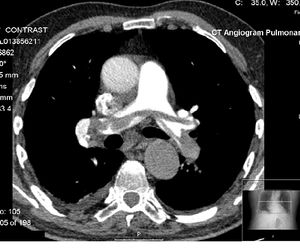

Example of a CTPA, demonstrating a saddle embolus (dark horizontal line) occluding the pulmonary arteries (bright white triangle)

وتستخدم في تصوير الشريان والأوردة بدل من الأشعة التداخلية وهي أكثر أمانًا وتستغرق وقت قصير وتشخيص الجلطة الرئوية بدل التصوير النووي